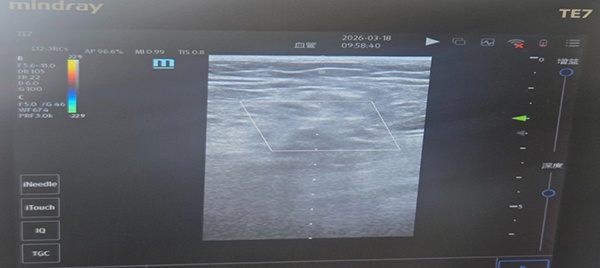

此次救治的最大瓶颈是患者存在临床极罕见血管发育异常,穿刺难度远超常规重症操作,检查发现,患者双侧股动脉发育性重度狭小、管腔极度狭窄,内径不足0.5cm,体表触诊完全无法扪及动脉搏动;常规二维床旁超声无法辨识血管解剖形态,仅能通过彩色多普勒超声捕捉到极微弱、纤细的线状血流信号,血管条件远低于临床有创穿刺最低阈值,常规盲穿、普通超声引导穿刺均无成功可能,属重症动脉穿刺领域极高难度罕见病例。